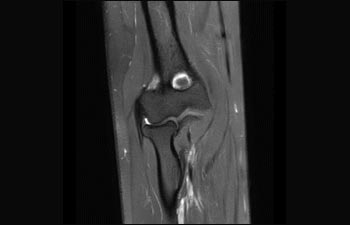

1De acuerdo con un estudio interno en el que se compara el flujo de trabajo con el equipo de RM Achieva. 2 ComforTone estará disponible con Prodiva 1.5T en el cuarto trimestre de 2017 3 De acuerdo con un estudio interno donde se compara el flujo de trabajo en una combinación de aplicaciones cerebrales, musculoesqueléticas, de columna y de cuerpo con el equipo de RM Achieva 4 La operación normal se define como una adquisición típica realizada con suministro continuo de electricidad, así como de refrigeración del imán, sin incluir las actividades de servicio 5 En función del contrato y de la disponibilidad local 6 Con "otros equipos de RM" nos referimos a equipos de RM de 1,5 T de 60 cm para exámenes de cuerpo entero